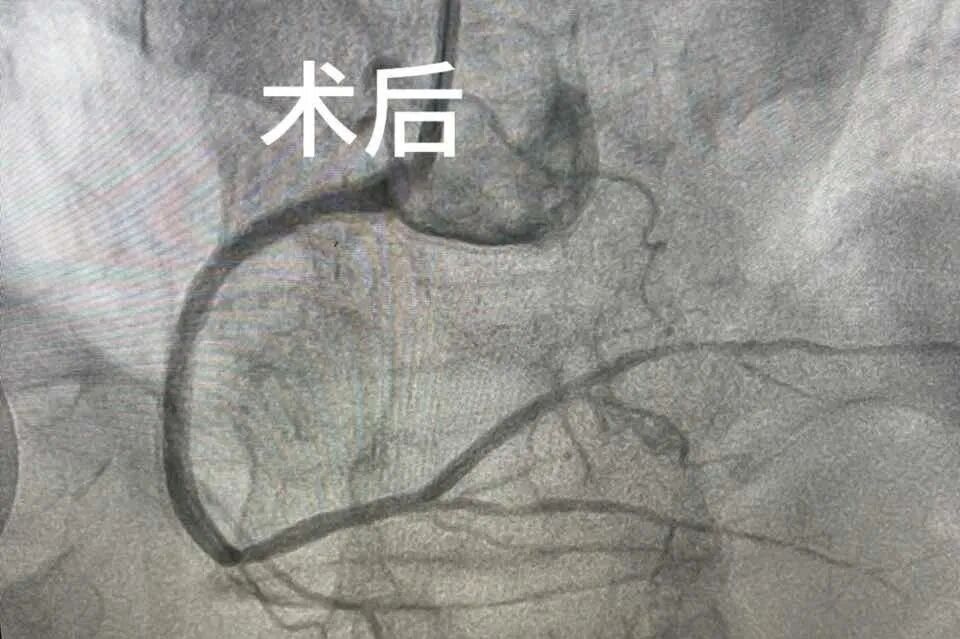

“情况危急,立刻启动胸痛流程!”急诊科通过“医警联动”联系上了患者家属,充分沟通后,为张大伯进行了冠状动脉介入手术。及时的救治,使他转危为安,之后在心血管内科住院治疗,现已能下床行走。